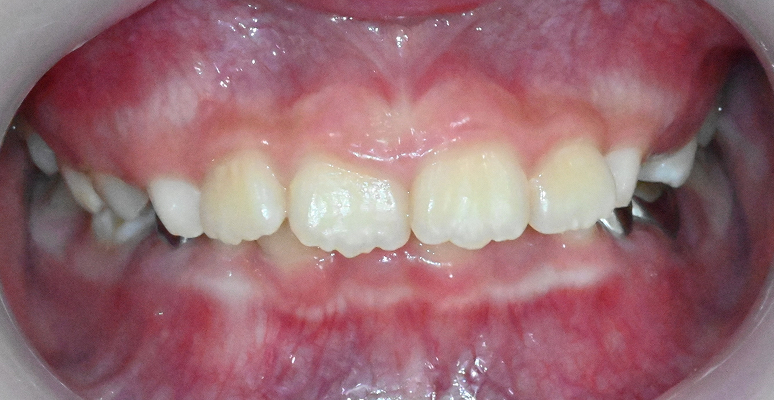

턱 성장 방향과 교합을 조기에 바로잡아

평생 바른 치열과 얼굴 균형을 만듭니다.